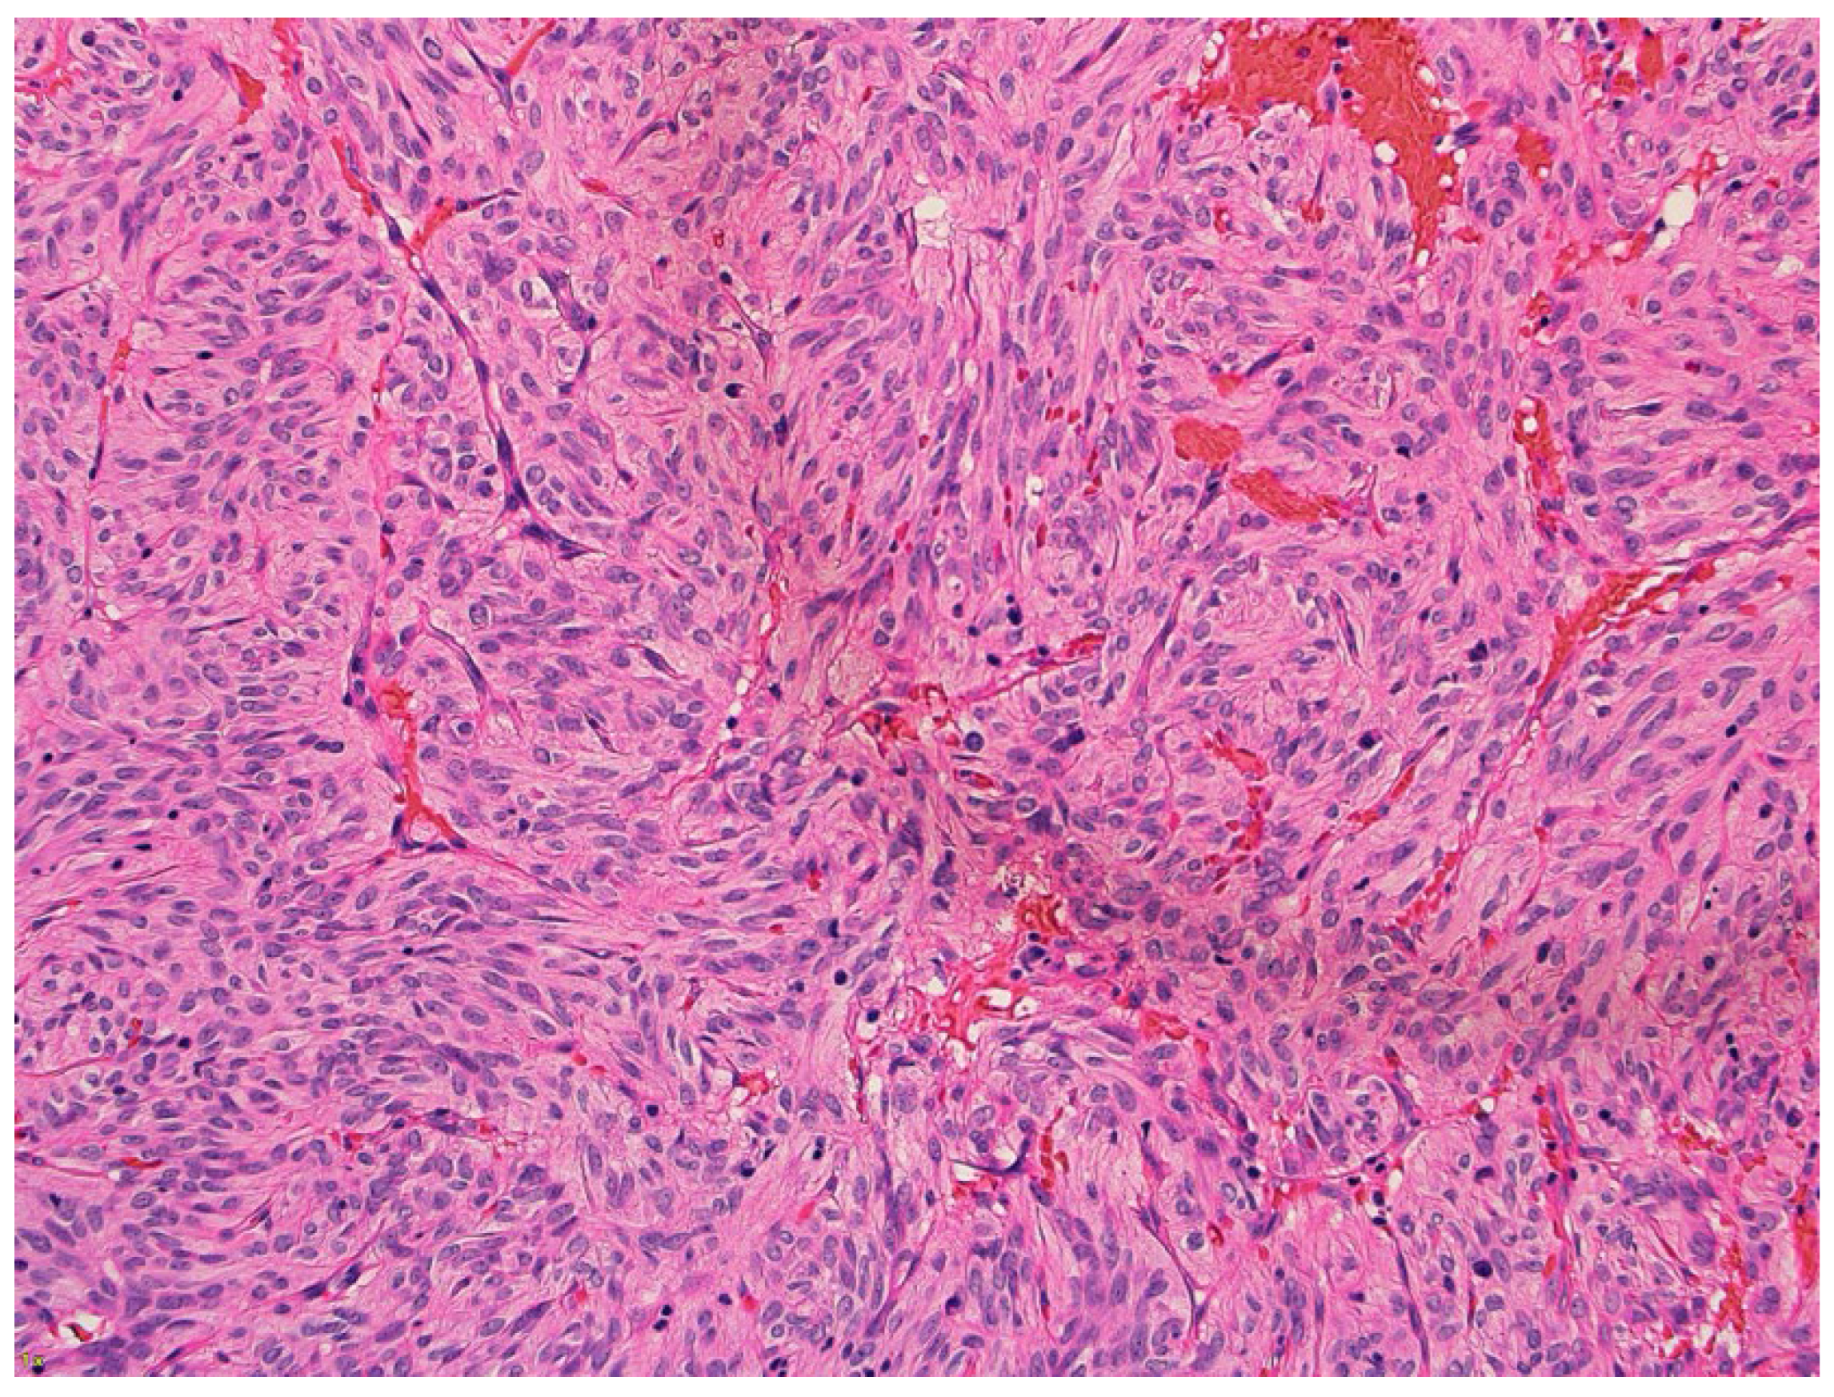

2. Case Presentation